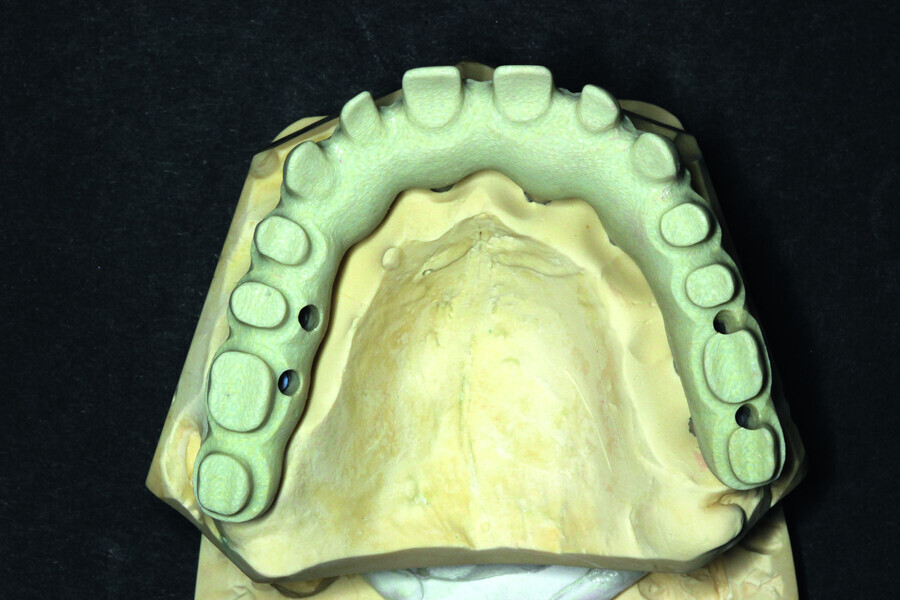

Fig. 10: Ready-made project of the supra-structure visible from the intragingival side.